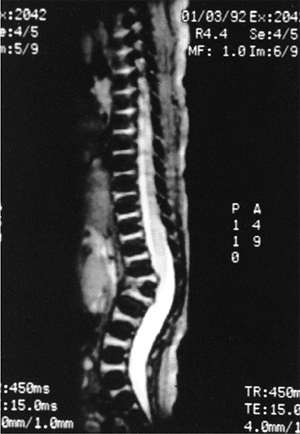

possible progression can be made. MRI should be obtained in most cases

because of the significant incidence of intraspinal abnormalities. In

addition, the location of the spinal cord and any areas of spinal cord

compression caused by the kyphosis can be seen on MRI. The cartilage

anlage will be well defined by MRI in patients with failure of

formation (Fig. 20.10); however, as with CT

scans and plain radiographs, MRI cannot reveal how much growth

potential is present in the cartilage anlage, and can only help one to

estimate the probability of a progressive deformity.

![]() |

|

Figure 20.10

Magnetic resonance image (MRI) of type I congenital kyphosis. Failure of formation of the anterior vertebral body is demonstrated, but the growth potential of the involved vertebra cannot be determined. Note the pressure on the dural sac. |